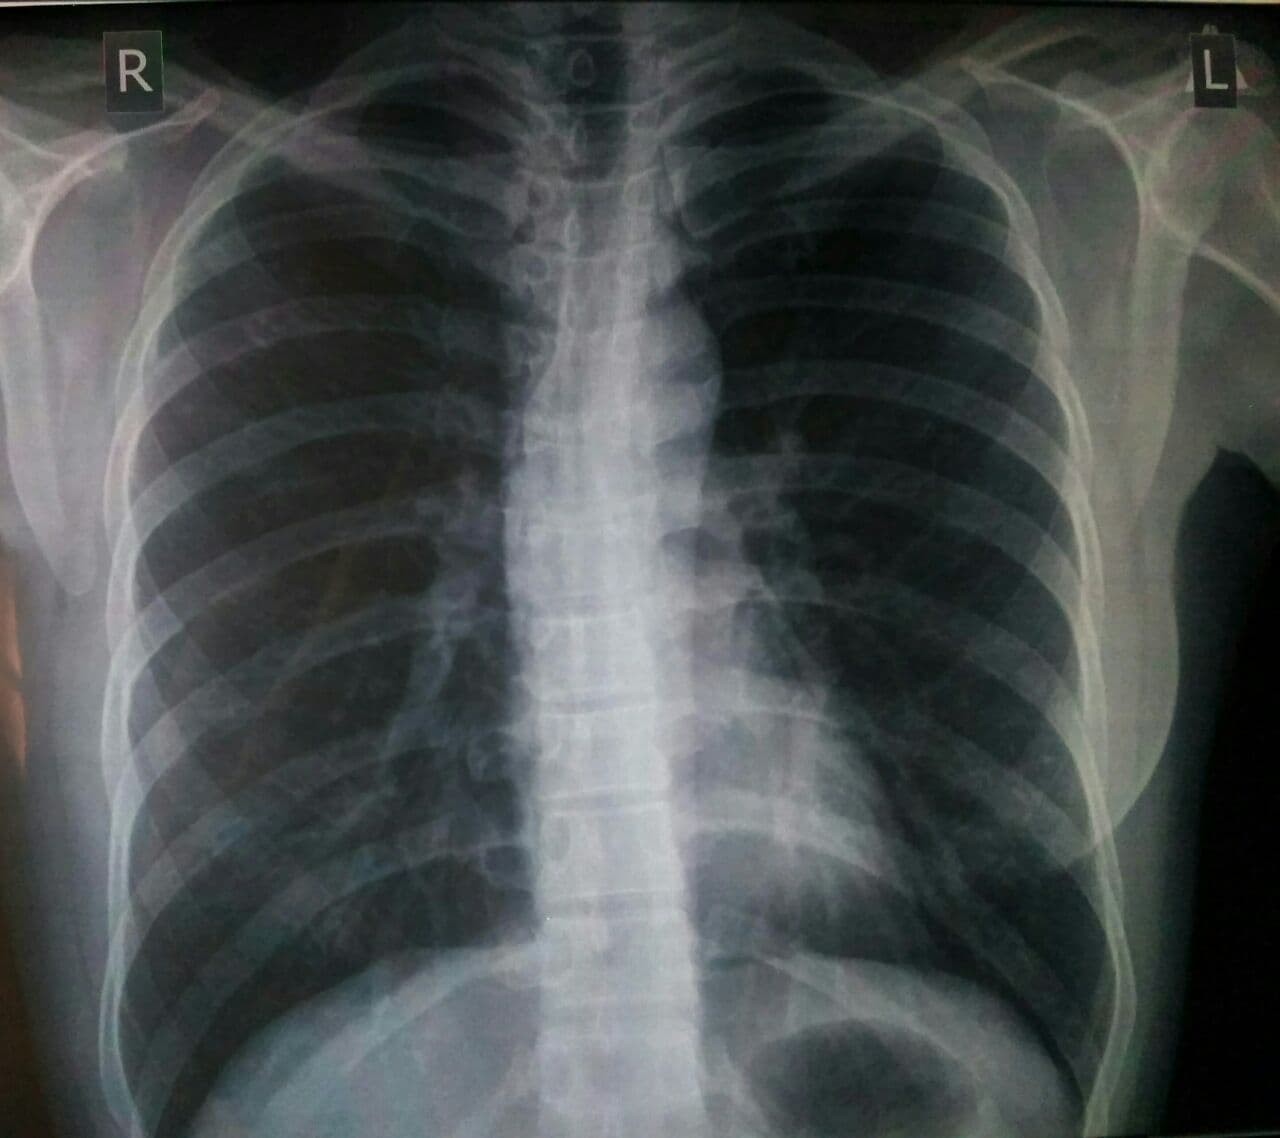

Снимок легких при туберкулезе является важным методом диагностики этого заболевания. На рентгеновских снимках можно увидеть изменения в легких, которые свойственны туберкулезу.

Рентген грудной клетки туберкулез

Рентген грудной клетки туберкулез

Рентгенография грудной клетки туберкулез

25

Рентгенография грудной клетки туберкулез

Рентген грудной клетки туберкулез

Рентген грудной клетки туберкулез

Фотографии снимков легких при туберкулезе

В данной статье представлены многочисленные фотографии снимков легких при туберкулезе, чтобы помочь вам понять, как выглядят изменения легких на рентгеновских снимках при этом заболевании.